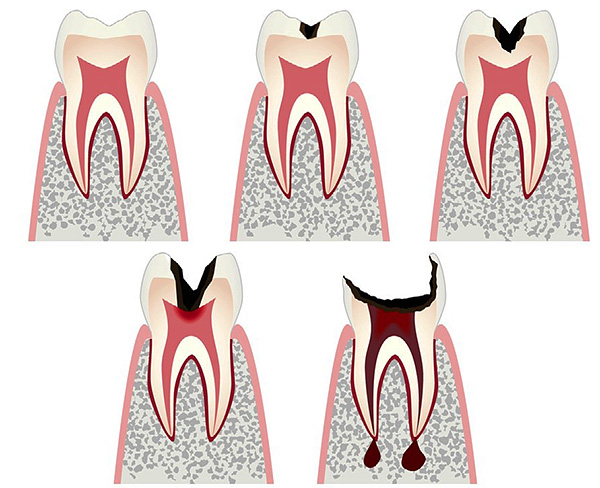

Para uma melhor compreensão do fato de que o processo já está em execução, é útil ter uma idéia sobre os estágios condicionais da cárie, o que acontece:

- Inicial (às vezes dizem sobre o estágio de uma mancha branca ou de giz - nesse estágio, apenas ocorre uma desmineralização do esmalte dentário);

- Superficial (esmalte dentário destruído);

- Médio (já existe dentina ativa sob esmalte protetor);

- Profundo (o processo patológico se aproxima da câmara pulpar do dente).

Na fase de cárie secundária, via de regra, é observada uma destruição bastante rápida da dentina, cuja estrutura porosa é preenchida com muitas bactérias cariadas. No entanto, a forma mais grave e negligenciada de cárie é a forma profunda, quando uma cavidade profunda e cárie se forma no contexto da rápida destruição da estrutura da dentina. Ao mesmo tempo, apenas alguns milímetros (muitas vezes até frações de milímetro) permanecem na polpa, e o fundo da cavidade é coberto com tecidos dentários amolecidos, pigmentados e deteriorados. A cárie profunda nominal é a mais perigosa em termos de transição para uma doença mais grave - a pulpite.